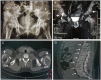

We report a case of a 29-year-old woman who suffered from severe bilateral inguinal pain and left mandibular mass. CT scan showed innumerable expansile osteolytic bone masses on the iliac wings, femur, ribs and vertebral bodies, diffuse skeletal osteopaenia, calyceal lithiasis on the right kidney and a left thyroid mass. Ionised calcium and intact parathyroid hormone (PTH) were elevated. Parathyroid sestamibi scan showed a hyperfunctioning left inferior parathyroid gland. Biopsy of the left mandibular mass was consistent with brown tumour. The patient underwent parathyroidectomy of the enlarged parathyroid gland. Final histopathology, however, revealed parathyroid carcinoma, 4.7 cm in widest dimension, with capsular and vascular space invasion. The patient underwent repeat surgery, specifically, left thyroid lobectomy, isthmectomy and central node dissection. Intact PTH decreased from 681.3 to 74 pg/mL (normal range: 10-65) 24 hours postoperatively. Follow-up at 6 months showed normal serum calcium levels, size reduction of bone lesions and improvement of quality of life.